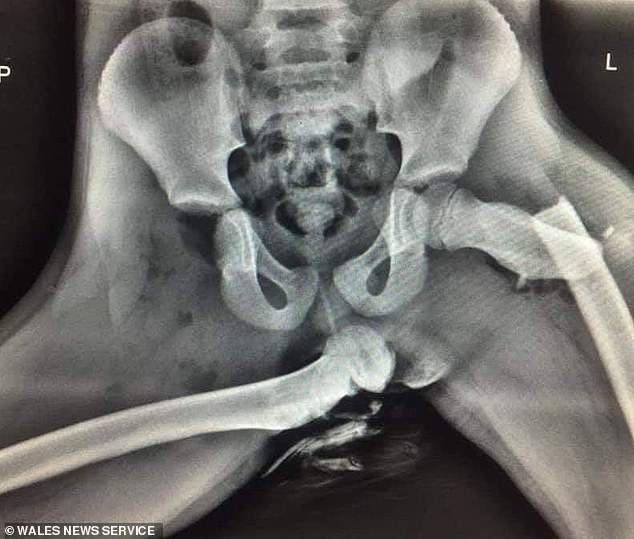

Un agent de la Poliția Rutieră a dezvăluit o radiografie șocantă a unei femei tinere, a cărei viață a fost schimbată în urma rănii de la șold provocată într-un accident, după ce aceasta și-a pus picioarele pe bordul mașinii.

Publicația Daily Mail informează că șoldurile femeii au fost complet zdrobite când a fost implicată într-un accident, în timp ce-și sprijinea picioarele de bordul mașinii. Un os al șoldului era rupt în timp ce celălalt era complet dislocat din articulația coxofemurală.

Un sergent de poliție din Țara Galilor, a postat fotografia pentru a emite un avertisment. El speră ca în felul acesta să-i conștientizeze pe pasagerii scaunelor din față să nu se relaxeze cu picioarele pe bord. Polițistul a spus: „Iată o radiografie cu răni groaznice suferite de o pasageră care stătea pe scaunul din față. Aceasta avea picioarele pe tabloul de bord în momentul unei coliziuni. Dacă vedeți că pasagerul din dreapta face la fel, opriți-vă din condus și arătați-i asta”.

Femeia din radiografie a supraviețuit, dar rănile provocate „i-au schimbat viața”. Punerea picioarelor pe tabloul de bord nu este în prezent ilegală în Marea Britanie. Polițiștii i-ar putea amenda cel mult pe șoferi. Și asta doar pentru că ar bloca vizibilitatea la oglinda laterală a mașinii.